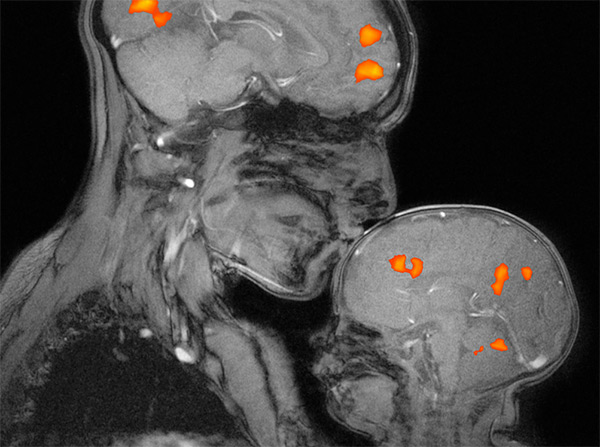

How much is universal, shared by all humans, and how much is specific and unique to each individual? How do learning and experience change how our brains work and who we are? Is there something we could see in a brain image that would be the earliest sign of a problem like autism, or dyslexia, or depression? Can we use this research to understand why human babies are so resilient to some kinds of trauma and so vulnerable to others?

These are the sorts of big picture questions that motivate developmental neuroscientists like us to come to work in the morning. Individual experiments tend to expand our knowledge a little bit at a time, and they sometimes fail (especially when you're asking a baby to sit still!). Together, though, they will allow us to build an understanding of ourselves and the ability to help. Hear and read more about what our lab is up to at the links below.